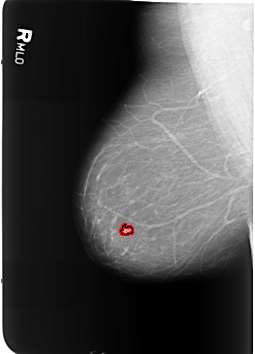

B_3369_1.RIGHT_MLO

FILE: B_3369_1.RIGHT_MLO.OVERLAY

TOTAL_ABNORMALITIES 1

ABNORMALITY 1

LESION_TYPE MASS SHAPE LOBULATED MARGINS CIRCUMSCRIBED-ILL_DEFINED

ASSESSMENT 4

SUBTLETY 3

PATHOLOGY BENIGN